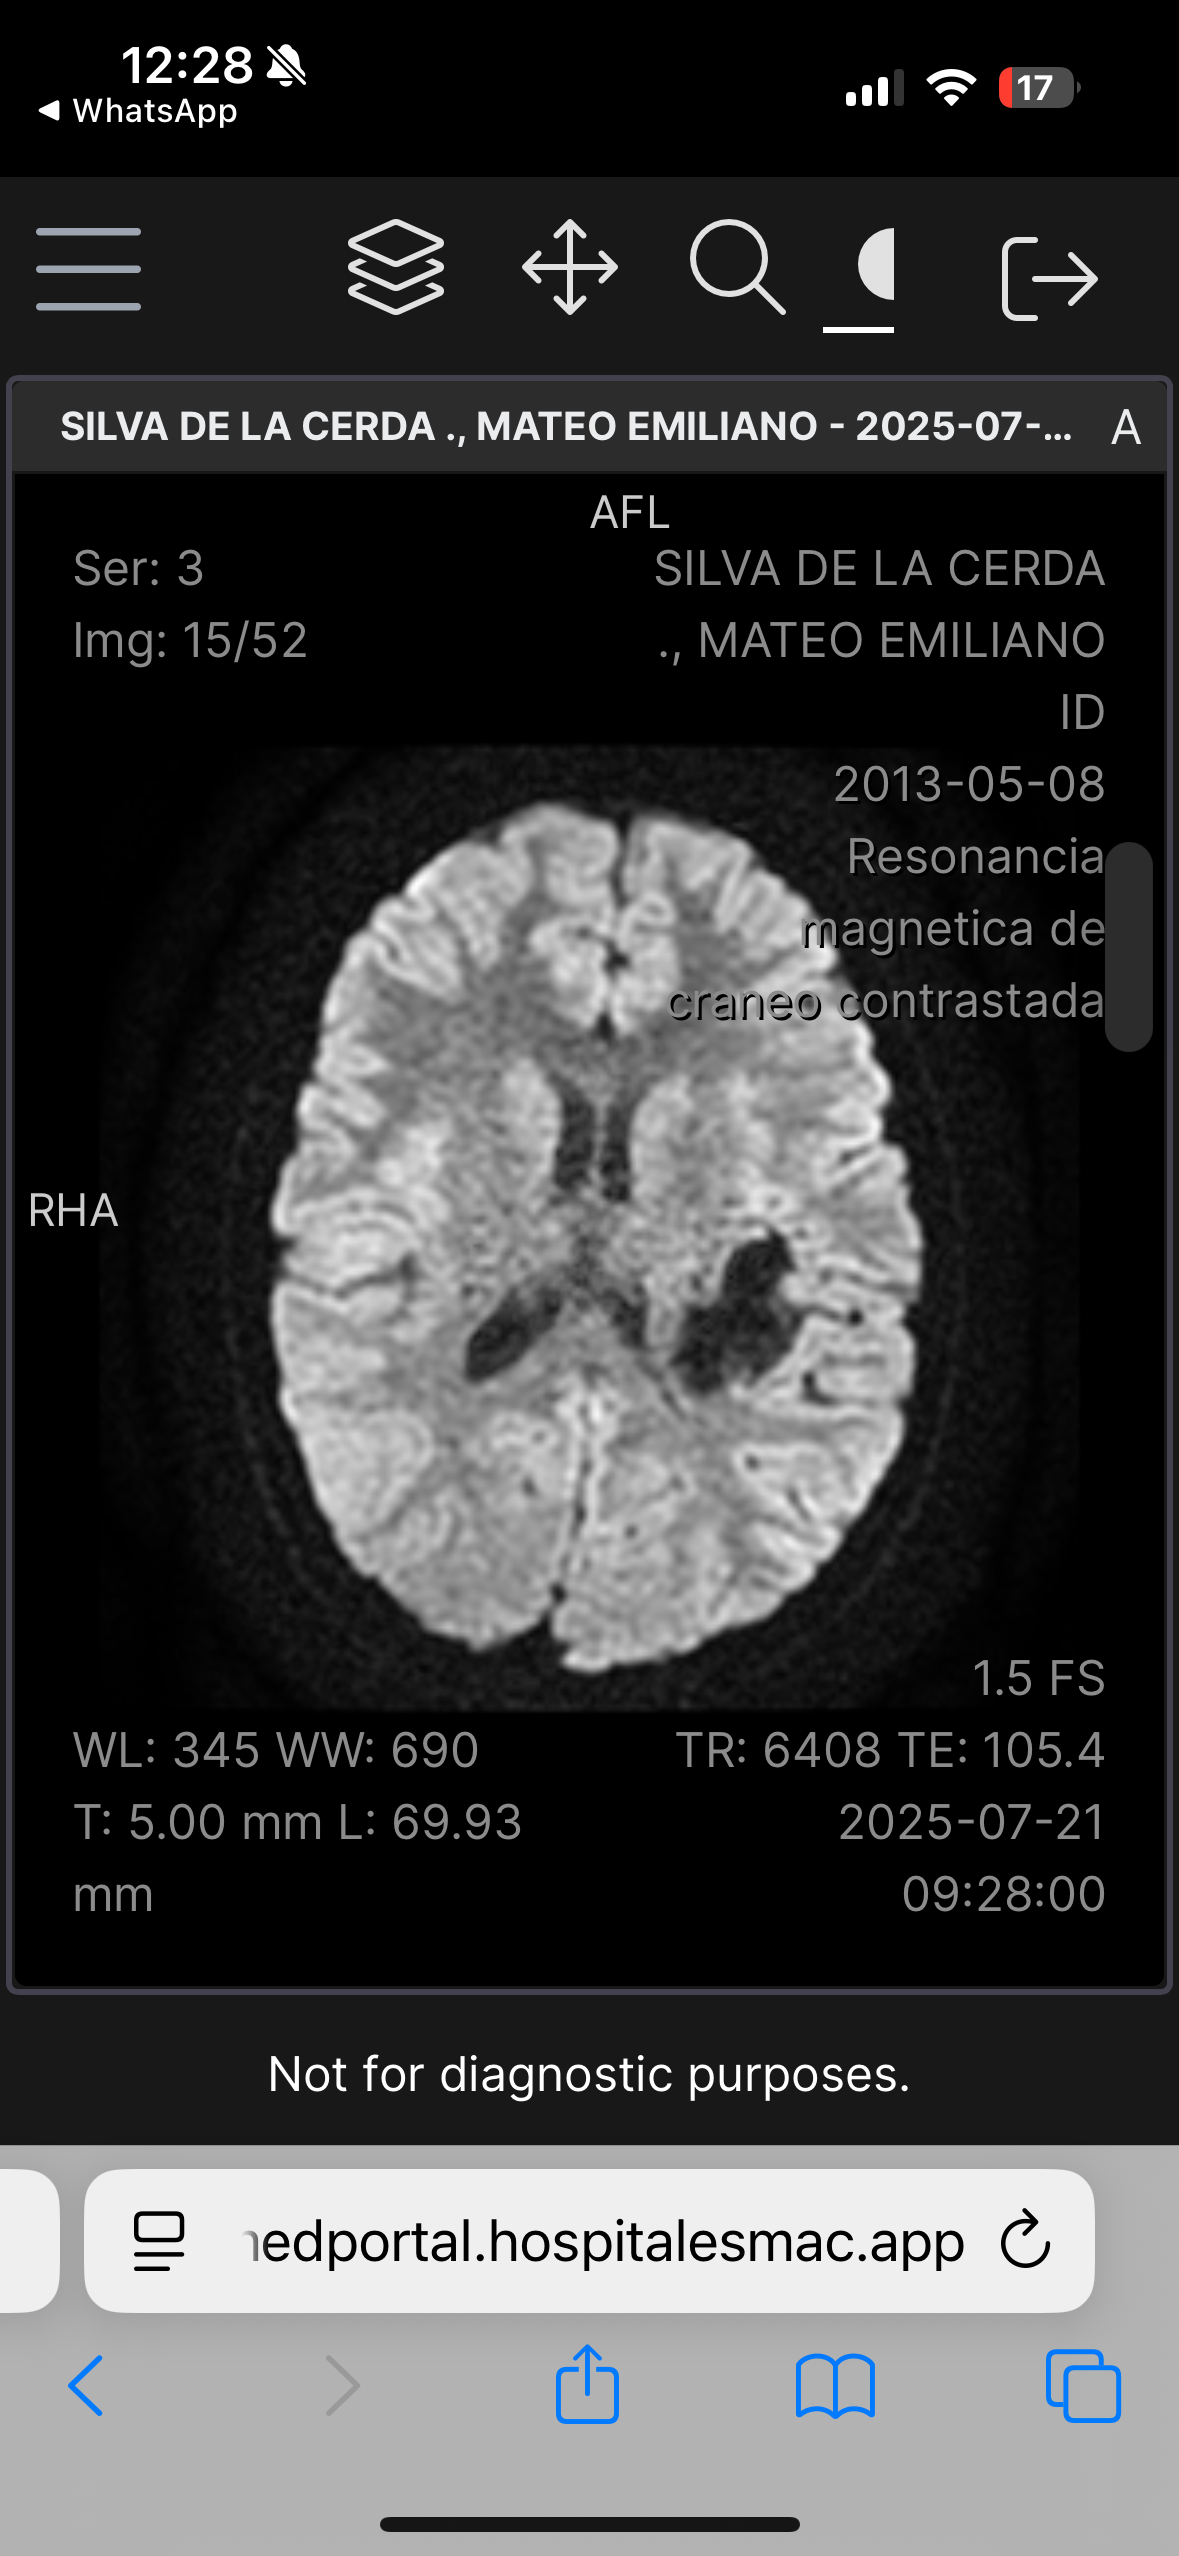

Hola, me llamo Mateo Silva De La Cerda, tengo 12 años, recientemente tuve un diagnóstico que cambió mi vida y la de mis papás, padezco una Malformación Arteriovenosa grado IV en la parte izquierda de mi cerebro, la cual hace un Nidus vascular. La complejidad de la malformación es por el aumento en la irrigación sanguínea los cual crea un tipo de “ nido” de venas y arterias, así como la profundidad en la cual se encuentra situada la malformación arteriovenosa en mi cerebro. Requiero una cirugía muy compleja, y la probabilidad de ocupar terapia intensiva posterior es muy alta.